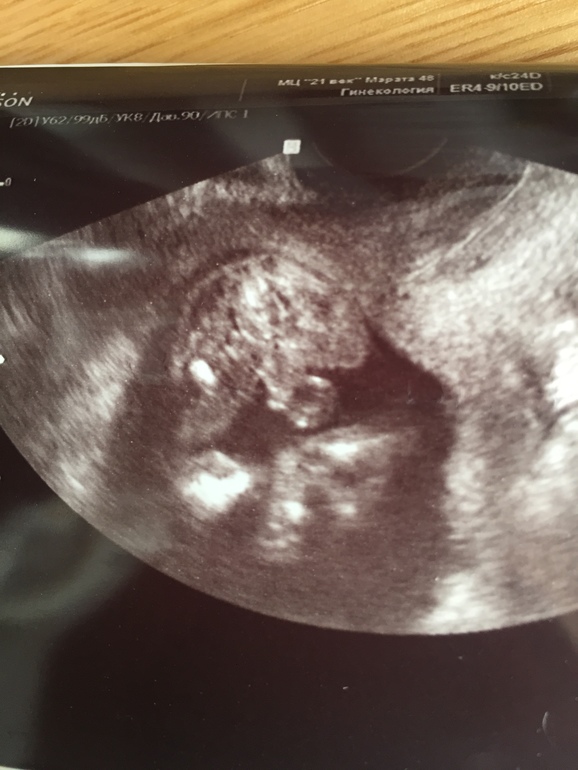

Классический вопрос)) Кто что видит на этом фото? )

Ровно 16 недель, справа там кусочек пуповины торчит. Ну и вид снизу естессно)

Пересмотрела уже кучу фоток разных узи) Я так поняла, что на этом сроке и у мальчика и у девочки почти одинаковый вид, но можно как-то отличить яйки) и половые губы (там какие-то полосочки вроде) я смотрю и не пойму что там есть?))

Кто опытный в этих картинках, кто что видит?))

По данному УЗИ кажется, что мальчик. Странно что врач вам точно не сказал. У меня с сыном уже в 14 недель было все предельно ясно: мошонка и писюн. А уж на 16 то и подавно

Срок уже более чем достаточный чтоб пол разглядеть, и на 11 -то все видно) но не на этой фотографии.. надо с допплером пуповину отличить, Чисто по этому фото кажется мальчик